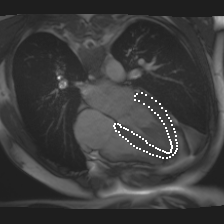

Accurate segmentation and motion estimation of myocardium have always been important in clinic field, which essentially contribute to the downstream diagnosis. However, existing methods cannot always guarantee the shape integrity for myocardium segmentation. In addition, motion estimation requires point correspondence on the myocardium region across different frames. In this paper, we propose a novel end-to-end deep statistic shape model to focus on myocardium segmentation with both shape integrity and boundary correspondence preserving. Specifically, myocardium shapes are represented by a fixed number of points, whose variations are extracted by Principal Component Analysis (PCA). Deep neural network is used to predict the transformation parameters (both affine and deformation), which are then used to warp the mean point cloud to the image domain. Furthermore, a differentiable rendering layer is introduced to incorporate mask supervision into the framework to learn more accurate point clouds. In this way, the proposed method is able to consistently produce anatomically reasonable segmentation mask without post processing. Additionally, the predicted point cloud guarantees boundary correspondence for sequential images, which contributes to the downstream tasks, such as the motion estimation of myocardium. We conduct several experiments to demonstrate the effectiveness of the proposed method on several benchmark datasets.